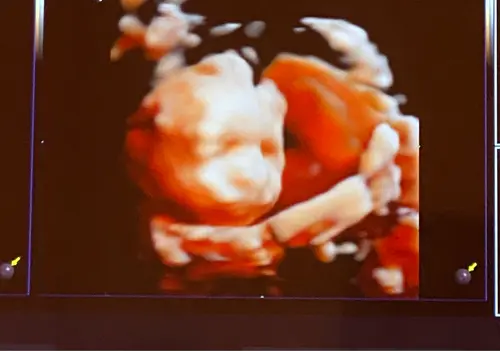

Het leukste vond ik toch de mogelijkheid om een 3D echo te laten maken 馃榿 en voorbeeldjes te zien van de buikbeeldjes, wil dit ook heel graag laten doen

Jaaa 240 video鈥檚 en foto鈥檚 hebben ze gemaakt, moet ee nog wel krijgen maar heb al een foto genomen 馃グ

Wij ook niet! Altijd problemen, of ze kijkt richting mijn rug of haar handen voor haar gezicht en het heeft echt 20 minuten geduurd, als het niet langer was en echt ineens liet ze haar gezichtje zien! Mega blij en dat dan nog met een voorliggende placenta 馃グ